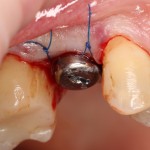

Затем лунка зуба адаптируется, в нее устанавливается имплантат, в данном случае Friadent XiVE диаметром 4.5 и длиной 13 мм:

Если не предполагается немедленная нагрузка (изготовление коронки на имплантат), первичная стабильность не является обязательной. Тем более, нельзя пытаться ее достичь, меняя положение и, особенно, погружение импланта. Если есть опасения, можно закрыть имплантат заглушкой, а саму лунку герметично ушить, используя свободный слизистотканный аутотрансплантат или (что разумнее) коллагеновую матрицу Mucograft Seal. Про последнюю обязательно расскажу вам, как только наберу достаточное количество клинических примеров.

Но в данном случае стабильность хорошая, на имплантат фиксируем формирователь десны, накладываем швы:

Еще один важный момент. Не нужно пытаться стянуть рану и добиваться плотного прилегания десны к формирователю. Любое натяжение слизистой оболочки ведет к ее изменению (прикрепленная десна становится подвижной), а процессы атрофии костной ткани ускоряются. Чем меньше тянем и перемещаем — тем лучше. Поэтому вполне разумно оставить вокруг формирователя открытую рану шириной 0.5-1.5 мм, она нормально заживет вторичным натяжением.